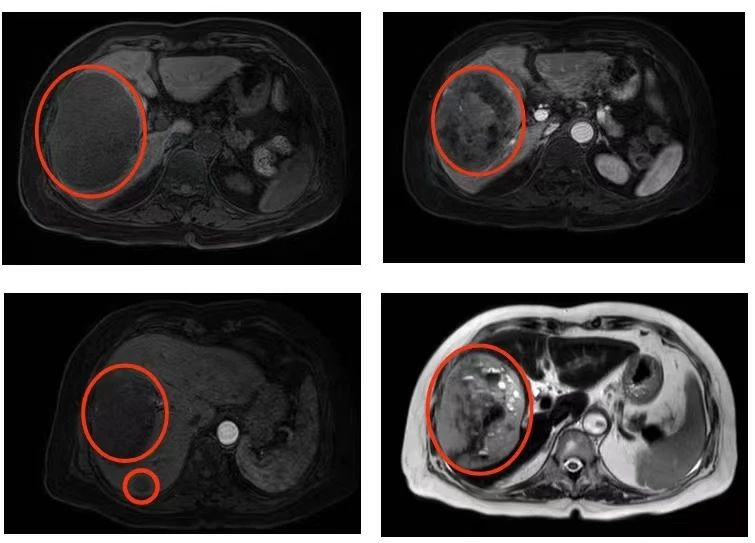

入院后,普外科迅速完善各项检查,MRI平扫+增强提示,肝右叶占位性病变11cmx10.6cmx7.6cm,怀疑其性质为恶性肿瘤。结合周奶奶病史、症状体征及相关辅助检查结果,考虑胃肠道间质瘤肝转移可能性大,而手术是唯一可能有治愈机会的方法

图示为肿瘤位置及大小